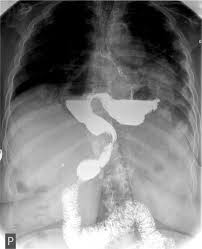

Barium Swallow Image Of Upside Down Stomach Download Scientific Diagram